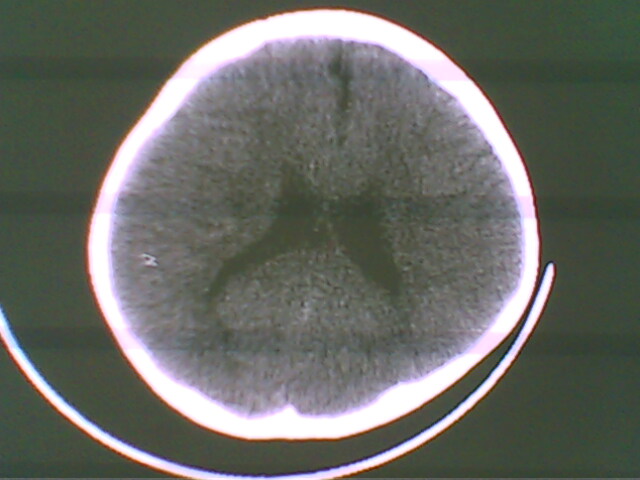

未见明显异常

未见异常

未见明显异常。

无异常发现.

图像有点差,未见明显异常。

正常.

未见明确异常。

图像稍稍有点差,未见明显异常。